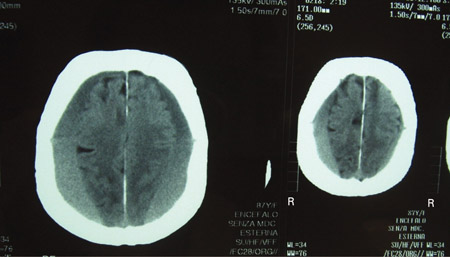

Hematoma subdural

TCs cranioencefálicas de um homem de 80 anos de idade com anormalidades da marcha e comprometimento cognitivo progressivo por cerca de 6 meses, mostrando um hematoma subdural crônico bilateral acima da convexidade cerebral

Adaptado de BMJ Case Rep. 2009;2009:bcr06.2008.0130